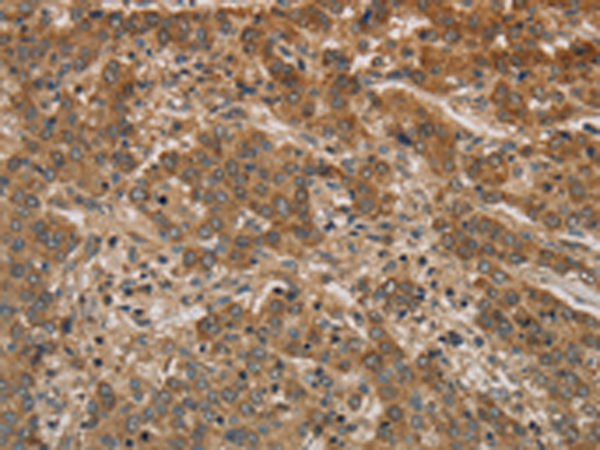

分类: 科研抗体货号: P11858别名: RANBP8应用: IHC反应种属: Human, Mouse